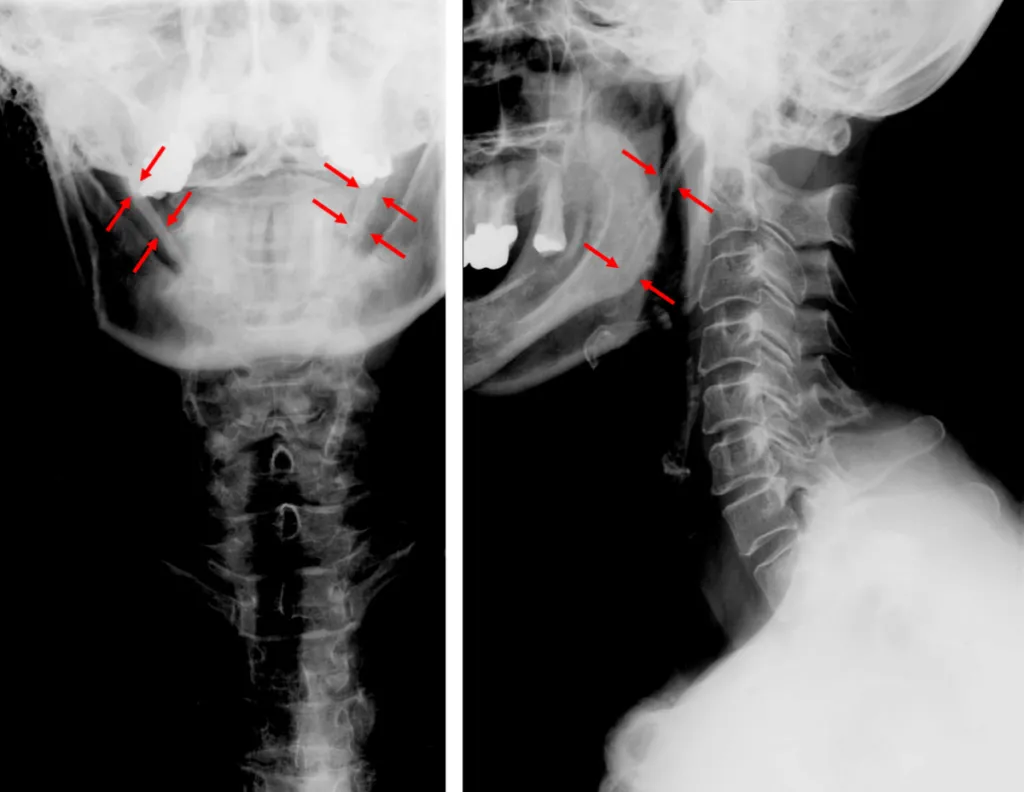

Imaging and Scans

Your doctor will also order imaging tests to get a picture of the bones and ligaments involved in Eagle syndrome. This includes X-rays, CT scans, and possibly ultrasound.

These scans will allow your doctor to take note of the length of your styloid process and other signs of Eagle syndrome.

Sometimes, an elongated styloid process is found incidentally during the evaluation of a panoramic X-ray at your dentist’s office.